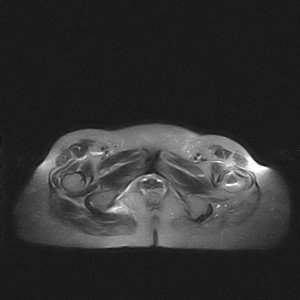

标题: MRI2691:读片病例2

我帮传的没看到病史!!!

图像太差了 1、右侧臀肌旁脓肿? 建议增强 2、左侧股骨头坏死并半脱位

1、左侧股骨头坏死并髋关节半脱位;

2、右侧臀肌感染,(可能褥疮所致)